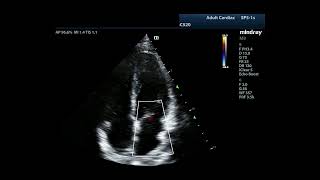

Тяжелая митральная недостаточность